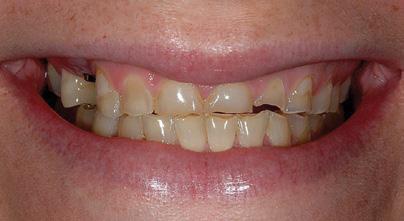

There Is Only One Smile That Matters. Yours!

You are in good hands! Dr. Makarita is the only accredited Fellow of the American Academy of Cosmetic Dentistry in Virginia.

BEFORE AFTER

At Tysons Aesthetic Dentistry Dr. Makarita has designed and equipped his practice with your smile in mind. Dedicated care and attention are just the beginning.

As a general dentist with a passion for aesthetic and cosmetic dentistry, whether a simple filling or a smile makeover, Dr. Makarita’s priority is to help you love your smile.

Since earning his doctorate from the Medical College of Virginia, Dr. Makarita has continually upgraded his skills and knowledge with continuing education so he can always bring you the most advanced options for all your dental needs.

Always welcoming new patients! Call 703-532-2020  8150 Leesburg Pike | Suite 503, Vienna VA 22182 www.ilovethatsmile.com

FREE SMILE EVALUATION In person or visit website for virtual smile consultation

Dr. H.R. Makarita

Accredited Fellow, American Academy of Cosmetic Dentistry

Master, Academy of General Dentistry

Master, International Congress of Oral Implantologists

Master, Las Vegas Institute for Advanced Dental Studies

to Love Your Smile? Dr. Makarita would love to meet you! About